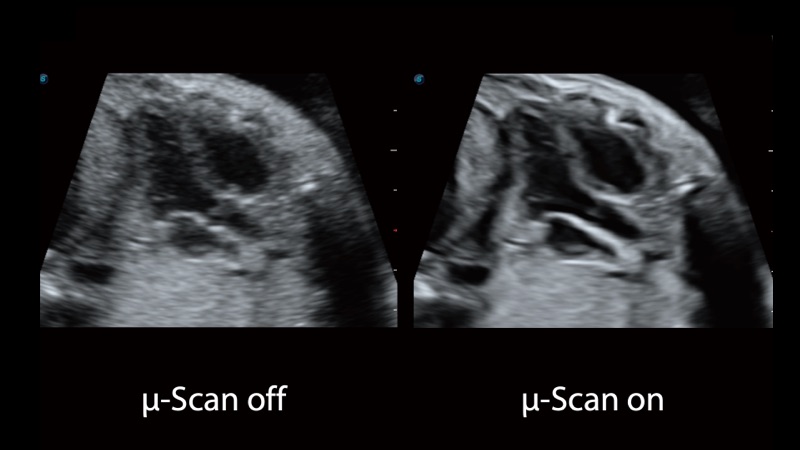

凭借公海贵宾会员检测中心医疗先进的成像技术和优异的探头技术提供的清晰的图像表现,您可以更自信地做出临床决策。